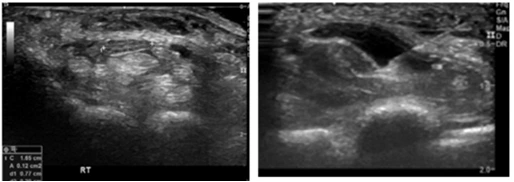

AD_4nXfJQ_QwlleyO0sinXZar2wyY3QNnJLaAHOr6Tyv3YZuN4hJ5UglSYg4l8b7IL6jXNwWaakzl2XJvbJfDSve6sOgChOhKImxoR7Jvbm17HP4MUV2OXclV_nn26vAat5D6ZMa-k0JwA?key=0_7uFam0xD727dkPNLVHRw 그림3. 환자 초음파 사진

우선 방사선 촬영과 초음파검사를 시행하였습니다. 방사선촬영에서 일부의 관절간격이 변화가 있고, 초음파 검사에서는 정중신경의 단면적이 12mm² 로 부어 있는 손목터널증후군이 함께 있었습니다. 환자분의 치료는 손목과 손가락의 프롤로치료를 하고 정중신경의 신경유착박리술 (hydrodissection)을 시행하였습니다.